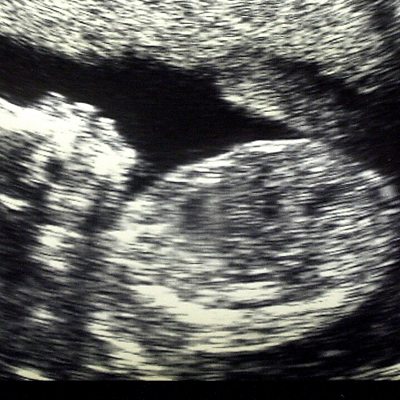

The nurture of intelligence begins in the womb